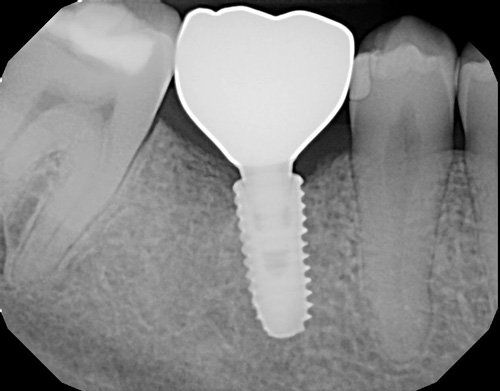

Patient needed multiple restorations, decay removed from upper teeth, crowns placed from canine to canine. Patient Missing 1st lower molar, implant and crown placed, chewing function restored. 2nd molar cracked, causing severe pain, nerve removed from tooth with root canal therapy